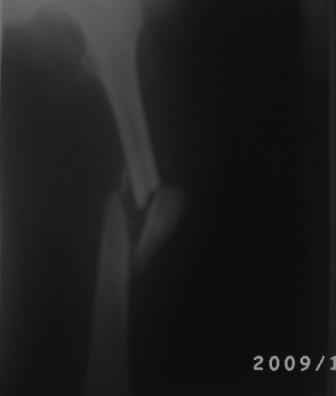

Добрый вечер, уважаемые коллеги.Произведена операция БИОС. Больной 35л, 3-месяца назад получил тяжелую сочетанную травму, после улучшение состояния доставлен к нам, Р-грамма прилагается.

Учитывая поворот большого костного осколка на 180гр. , произведена открытая репозиция, скелетирована только передне-наружная поверхность., антеградный и/м остеосинтез, и наш старенький ЭОП перестал работать, пришлось дистальную блокировку произвести в рентген кабинете под сериоскоп-Сименс, с большими трудностями.

И в конце выяснилось что имеется диастаз задне-внутренной стенки. Заново блокировать рентгенологи не разрешили.